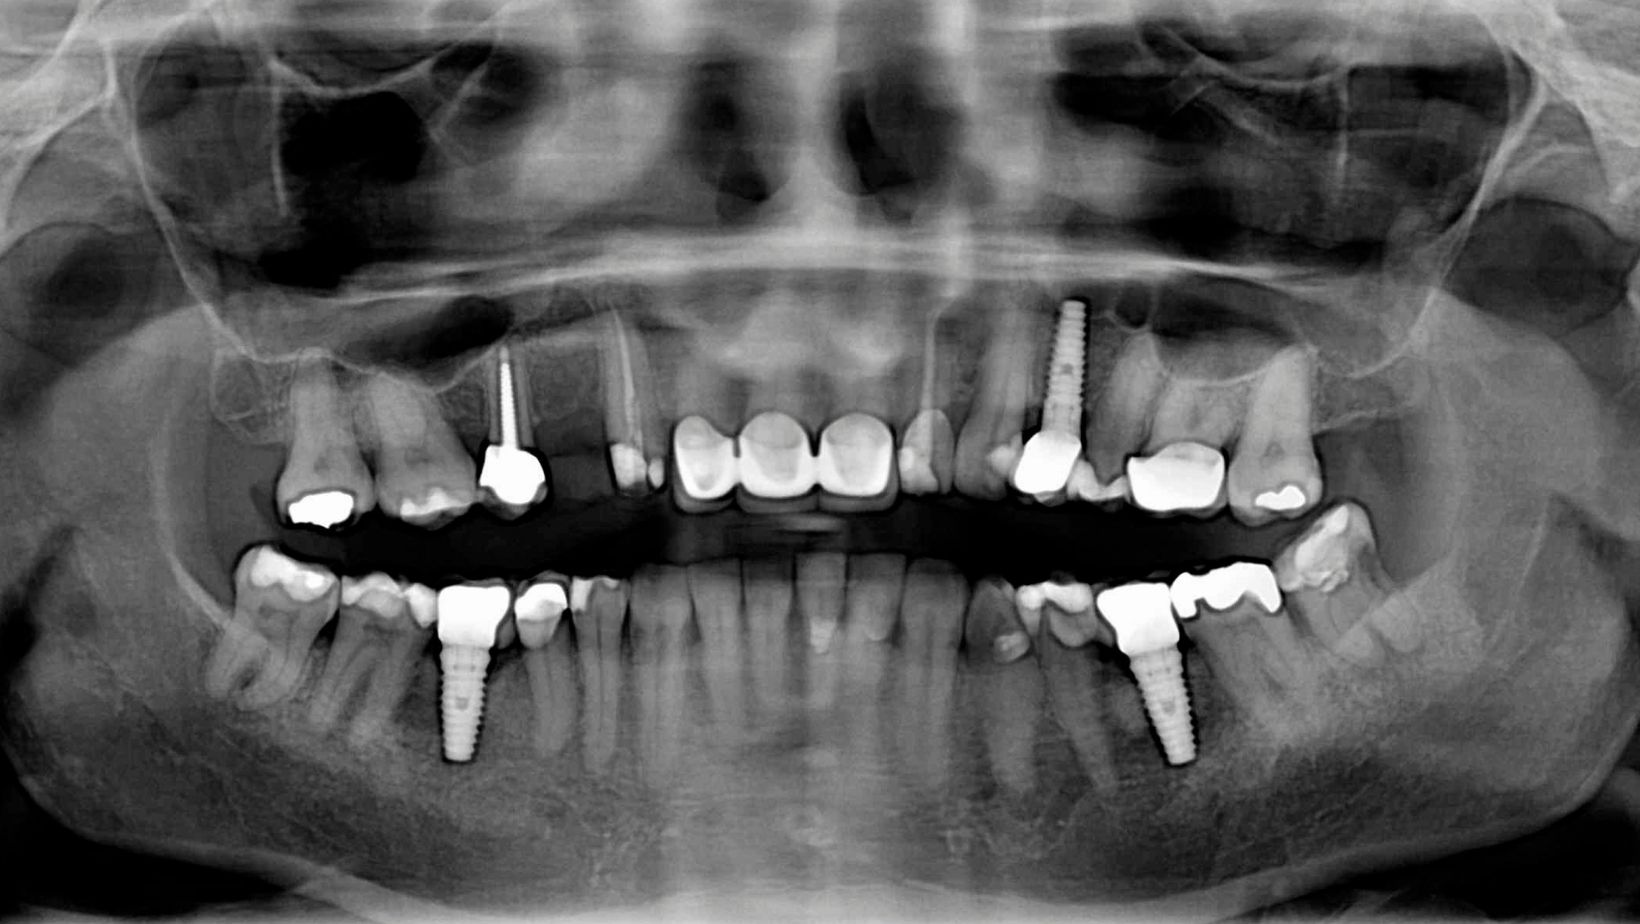

All-on-4 implants use four titanium posts fixed into your jaw to support a full arch of artificial teeth. Unlike traditional implants that may require more posts, this method uses fewer implants, which reduces surgery time and cost. The implant posts fuse with your bone, offering strong support for the new teeth. These teeth look and function like natural teeth.

This system is often called “All-on-Four” because all your teeth on one jaw are anchored to four implants. It is suitable if you have lost many teeth or will need full teeth replacement on your upper or lower jaw.